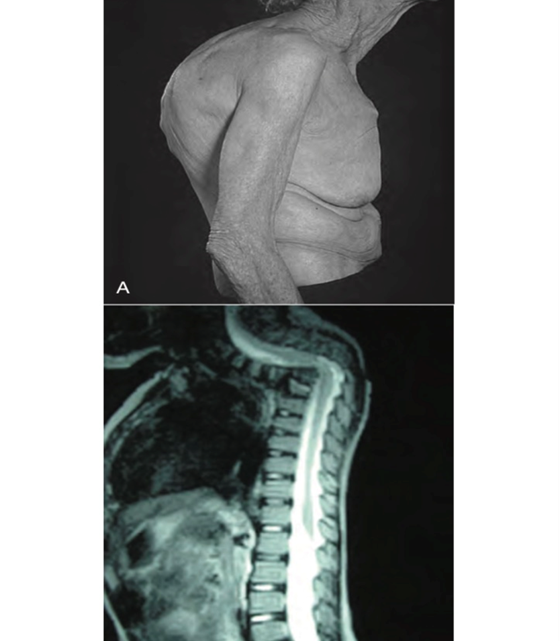

Barrel chest (Fig. 14-9), results from compromised respiration as in, for example what diseases?

and characteristics of Barrel chest?

A

chronic asthma, emphysema, or cystic fibrosis.

2) The ribs are more horizontal, the spine is at least somewhat kyphotic, and the sternal angle is more prominent.

3) The AP diameter approaches or equals the lateral diameter (a ratio of 1.0 or even greater), there is most often a chronic condition present.

Barrel Chest that results from compromised respiration as in, for example, of what disease AGAIN? Barrel Chest presents with an increase in the anteroposterior diameter (a ratio of 1.0 or even more) as well as a widened costal angle (greater than 90 degrees)

chronic asthma, COPD, emphysema, or cystic fibrosis.

# Findings associated with disorders Barrel chest with kyphosis, prominent sternal angle, and obstructive pulmonary disease is associated with

Chronic disease